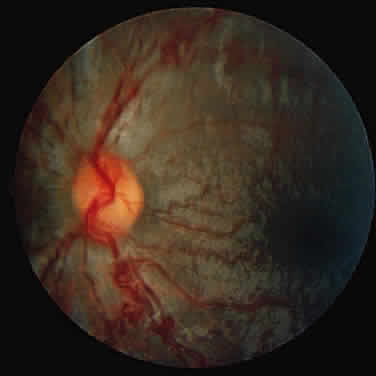

tissue. In McKusick V (ed): Hentable Disorders of Corrective Tissue, pp 521, 641, 646. St. Louis, Mosby, 1972 9. Spranger J: The systemic mucopolysaccharidoses. Ergeb Inn Med Kinderheilkd 32: 165, 1972 10. Collins M, Traboulsi E, Maumenee I: Optic nerve head swelling and optic atrophy in the mucopolysaccharidoses. Ophthalmology 97:1445, 1990 11. Kenyon K, Quigley H, Hussels IE: The systemic mucopolysaccharidosis: Ultrastructural and histochemical studies

findings. Br J Ophthalmol 68:590, 1984 34. Braun S, Aronovich E, Anderson R et al: Metabolic correction and cross-correction of mucopolysaccharidosis type

of N-acetyl-galactosamine-4-sulfatase. Biochem Biophys Res Commun 60:1170, 1974 50. Young R, Kleinman G, Odemann R et al: Compressive myelopathy in Maroteaux-Lamy syndrome: Clinical and pathological